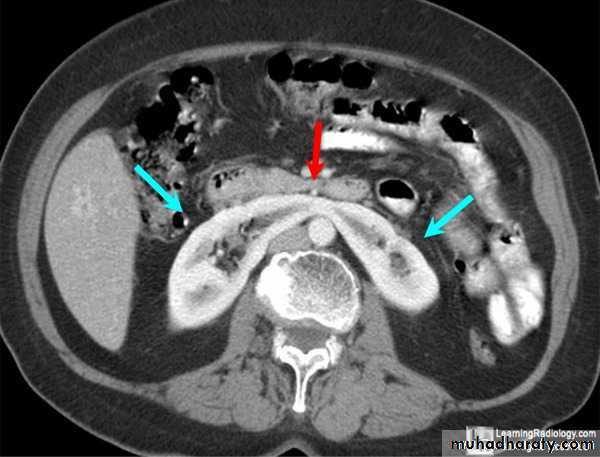

Fusion of lower pole of both kidneys by bridge of renal tissue (isthmus) crossing in front of aorta, spine and IVC.

IVU shows :

The kidneys at low position .

Close to the spine with long axis parallel to the spine .

Mal–rotation manifested by medially directed calyces.

The renal pelvis and ureters are anterior and lateral in position .

Fusion of upper poles is rare.

HORSE –SHOE KIDNEY

HORSE SHOE KIDNEY